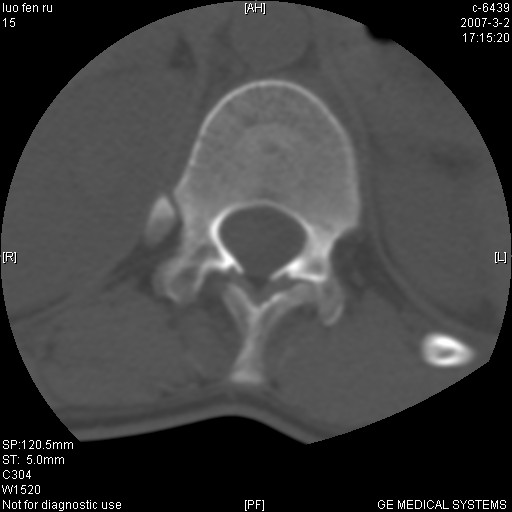

边缘硬化、增生复合陈旧性骨折。

结核:好发于胸椎,其次为腰椎,相邻椎体受侵,椎间隙变窄,椎体变扁,椎旁或腰大肌冷脓肿形成。

许莫氏结节形成

t11椎体前缘不规则形骨质破坏,周围有硬化边,软组织肿块不明显,首先考虑:骨嗜酸性肉芽肿 。期待随访结果。